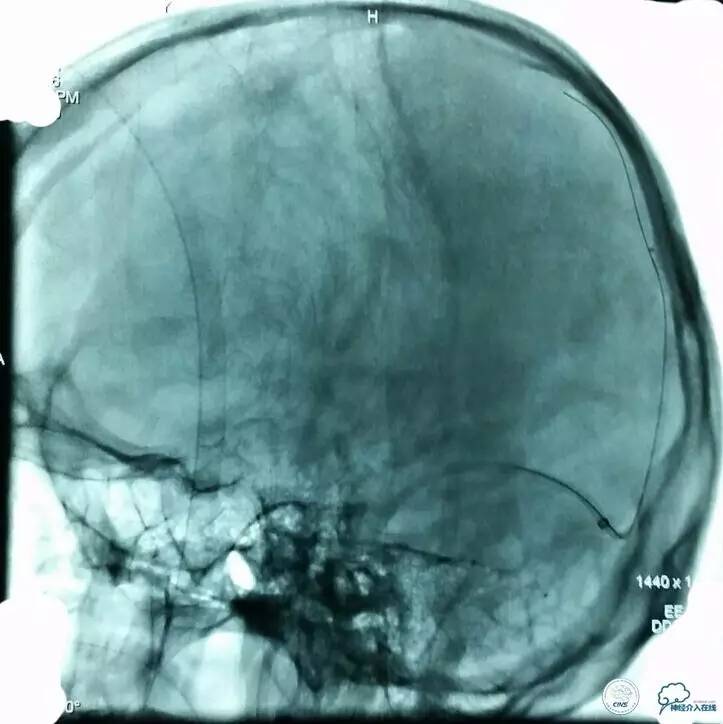

▼8F-Guiding 导管+6F-Navien 导管到位,微导丝选入上矢状位窦内。

▼Solitare6mm-30mm支架放于近端窦汇处,血栓中,5分钟后取栓。

▼取栓后再次,微导管到矢状窦: